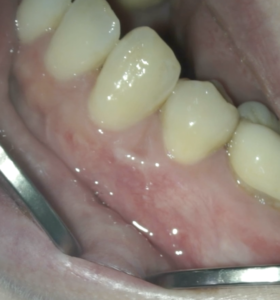

Post-op 1yr Endo test(2026.1.20)

術前の臨床症状は消失した。

外科の切開線の痕もない。

まさに完治だ。

術後の骨欠損は完治した。

ということで経過観察も終了である。